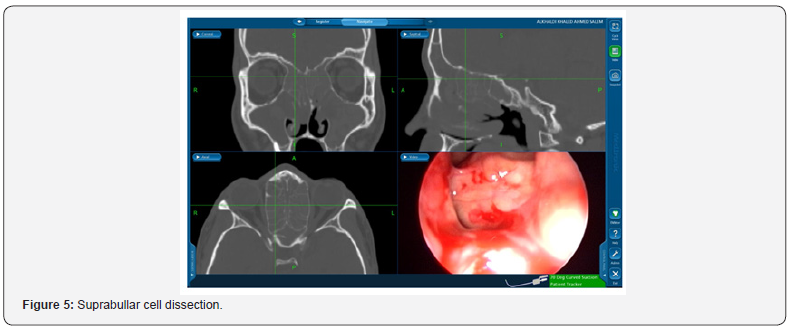

Suprabullar cells are also a recognizable cause of recurrence where is can be wronged for base of skull during primary surgery and left untouched [12]. That represents 11% of the findings in the revision cases in this study such as the illustrated case in Figure 5. In another recognizable cause 24% of the revised patients had lateralization of the middle turbinate Figure 6. This lateralization was found to be due to scarring between the turbinate and retained air cells or uncinate process 13%, 11% respectively. Other causes include neo-osteogenesis, which believed to be caused by failure to preserve normal mucosa [13]. Neo-osteogenesis as seen in Figure 7 presented 5% of our findings.